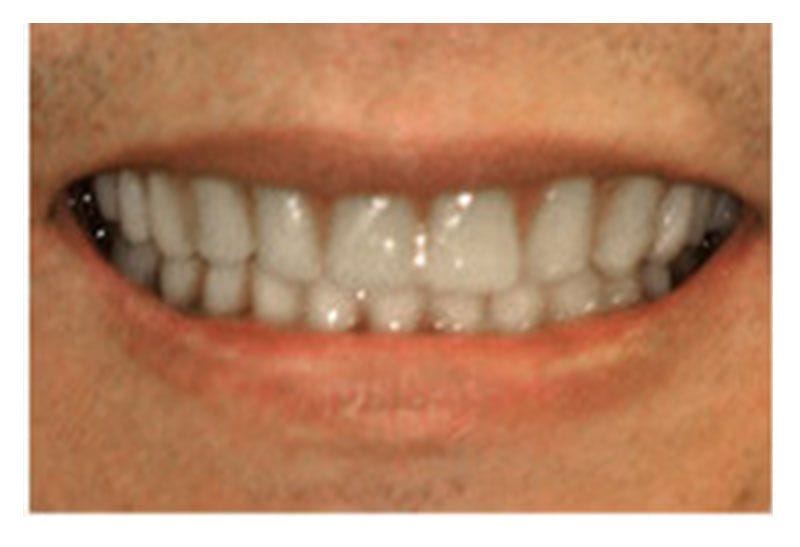

沈先生,上下顎的牙齒均脫落,必須配戴全口假牙,造成日常飲食十分不便,常常在吃東西時無法咀嚼,並且假牙時常脫落,為此每天感到焦慮,經過診所治療,現在已經不用安裝假牙了,並且在吃東西時也方便許多,經治療後的結果令沈先生相當滿意。